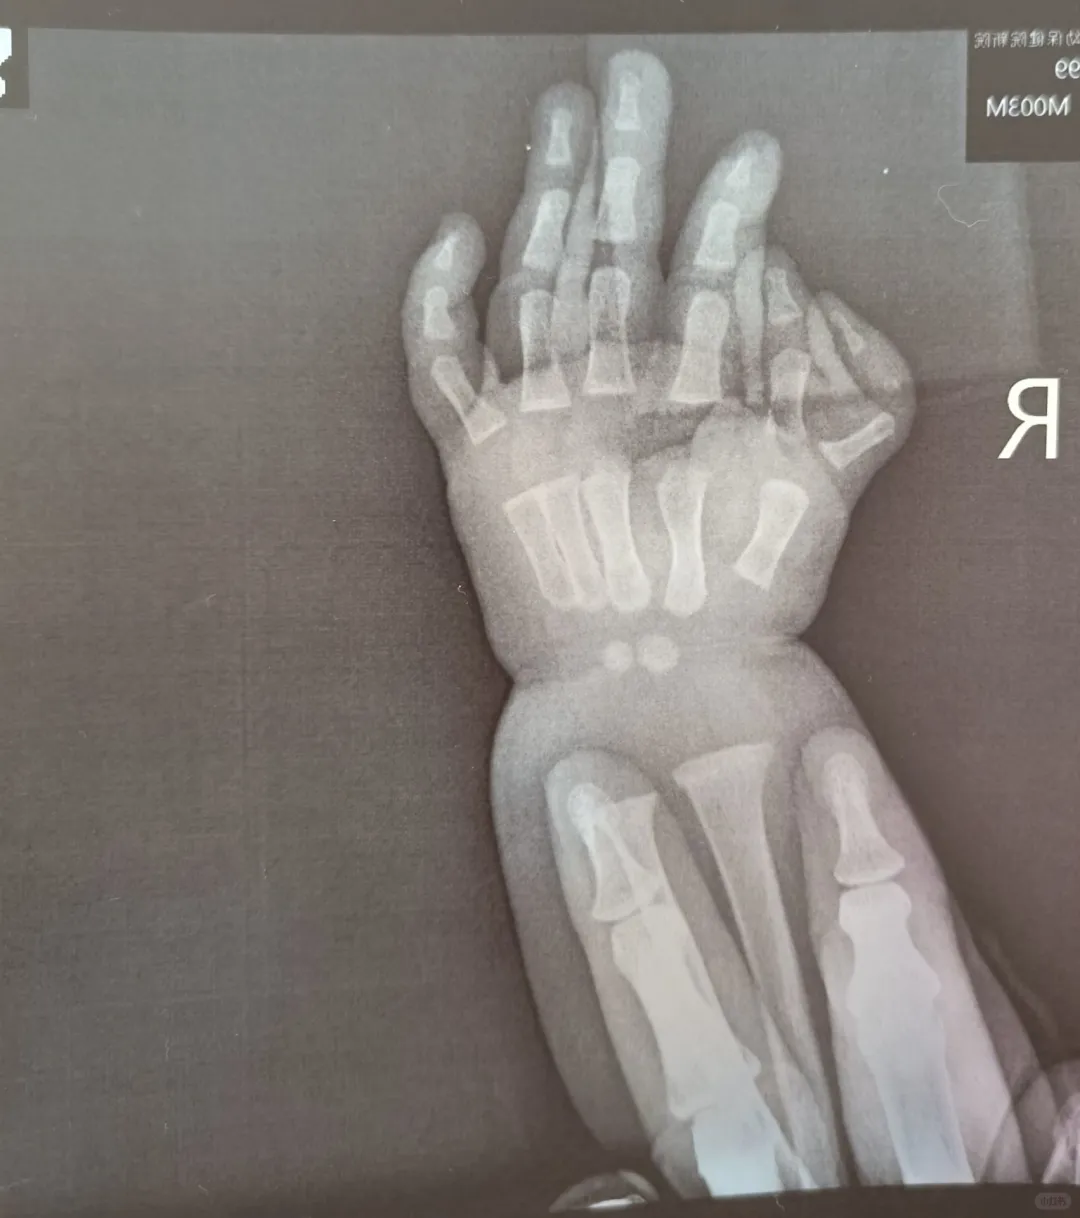

多指手术择医生篇

#多指手术#多指宝宝#蟹钳指#